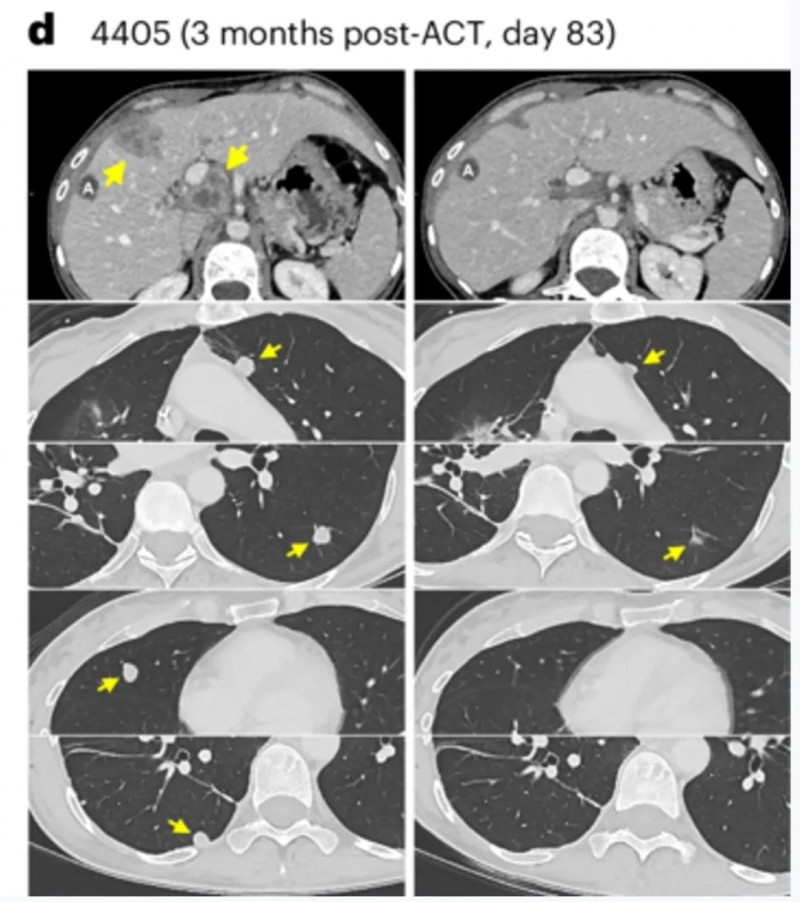

已有研究证实,NY-ESO-1是安全性与有效性良好的潜在癌症免疫治疗靶点,因此我们选择其作为本研究中T细胞受体工程化T细胞(TCR-T细胞)的理想靶向抗原。...